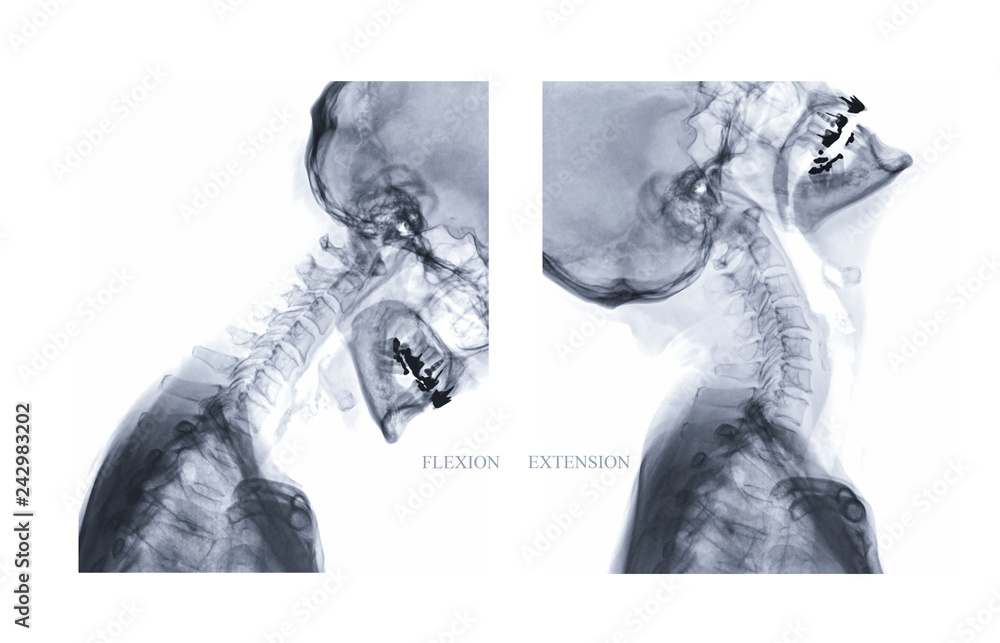

Flexion and extension cervical spine xrays 4 months postoperatively

Flexion and extension cervical spine xrays 4 months postoperatively Cervical Flexion And Extension X Rays the aim of this review was to investigate whether flexion/extension (f/e) radiography adds diagnostic value to ct or mri in the detection of cervical. the cervical spine series is a set of radiographs taken to investigate the bony structures of the cervical spine, albeit commonly replaced by the ct, the. the cervical spine flexion and extension views. Cervical Flexion And Extension X Rays.